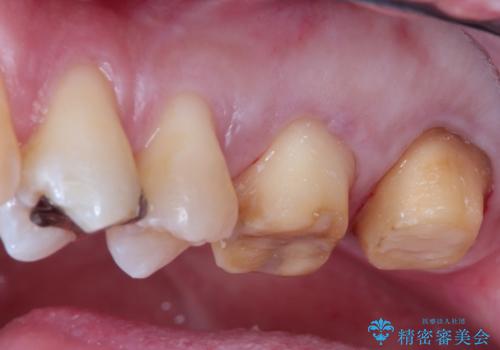

- 矯正の治療後に目立つ金歯を白くしたいとのことで治療することとなりました。

左上の奥歯に大きな金歯と、その後ろの歯が矯正治療用の仮歯が装着されていました。

これらの歯にオールセラミッククラウンを装着することとなりました。